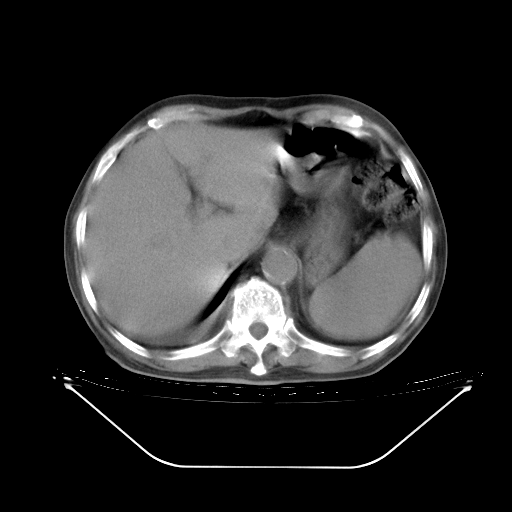

胸腹部CT,诊断意见:左上肺叶钙化灶、左侧胸膜局限性增厚并钙化、胆囊炎。描述部分肺组织呈磨玻璃样改变。

今天复查肺部CT,发现双肺广泛磨玻璃样改变。所以我把3月19日和5月9日相隔50天的肺部CT上传。请大家会诊。

5月9日肺部CT(在4月27日齐鲁医院肺部CT描述部分肺组织磨玻璃样改变,12天后肺组织广泛磨玻璃样改变)

大致读了系列胸部CT:纵隔窗无明显异常,肺窗:从4、27至今:主要是双肺中下野外带可见毛玻璃样改变,目前处于急性肺泡炎阶段,至于原因考虑1、结替组织或胶原血管性疾病所致?2、恶性疾病如恶组在肺部所致的表现或细支气管肺泡癌?3、药物或其它原因如肺蛋白沉着症所致肺泡炎目前不太可能?总之,明天就去请我院的呼吸科、感染科、血液科和临免专家会诊哈。